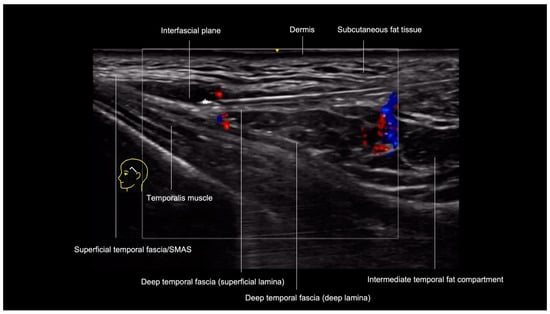

3.1. Temporal Region

3.1.1. Sonographic Anatomy

- Epidermis: hyperechoic line.

- Upper dermis: hypoechoic homogeneous layer.

- Lower dermis: usually more echogenic layer than the upper dermis.

- Subcutaneous fat tissue: a hypoechoic layer composed of fat lobules and hyperechoic septae.

- Superficial temporal fascia/Superficial musculoaponeurotic system (SMAS): linear hyperechoic layers enveloping the superficial temporal artery and vein.

- Sub-SMAS fat: also called innominate fascia, it is a hypoechoic layer composed of loose connective tissue and fat lobules. This is the interfascial plane.

- Superficial lamina of the deep temporal fascia: a hyperechoic line, which is juxtaposed to the intermediate temporal fat compartment.

- Intermediate fat compartment (loose areolar tissue): a hypoechoic triangular layer composed of fat lobules and hyperechoic septae. The middle temporal vein can be encountered in this layer.

- Deep lamina of the deep temporal fascia: a hyperechoic line, which is deep to the intermediate temporal fat compartment.

- Temporal muscle: a large hypoechoic structure above the bone, where the anterior and posterior deep temporal arteries are located.

- Temporal extension of the buccal fat compartment: a hypoechoic fat compartment adjacent to the lateral orbital rim, connected to the buccal fat pat. Easily recognized when patient is asked to open and close the mouth, this fat pad can be found under the deep lamina of the deep temporal fascia.

- Bone: a thin hyperechoic line with acoustic shadowing.